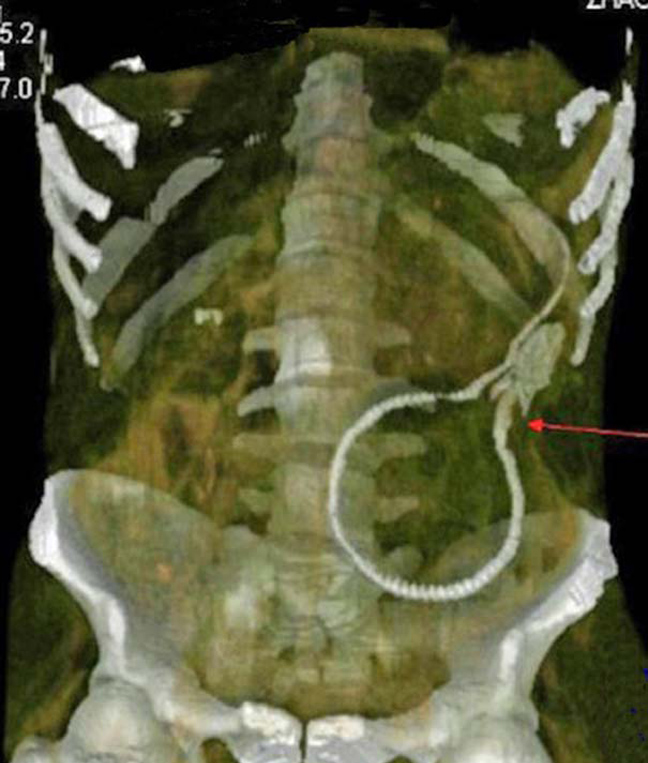

Δαχτυλίδι αρραβώνων Κλειδί Κουζινικά Χελι Μαγνητάκια Καρφιά 78 Κουτάλια και πιρούνια Φίδι

Ο,ΤΙ ΝΑ 'ΝΑΙ #φωτογραφίες Όταν μιλούν οι ακτινογραφίες! Αντικείμενα -και όχι μόνο- μέσα σε ανθρώπινα σώματα… 24·09·2013 13:33 16 σχόλια Δαχτυλίδι αρραβώνων Κλειδί Κουζινικά Χελι Μαγνητάκια Καρφιά 78 Κουτάλια και πιρούνια Φίδι